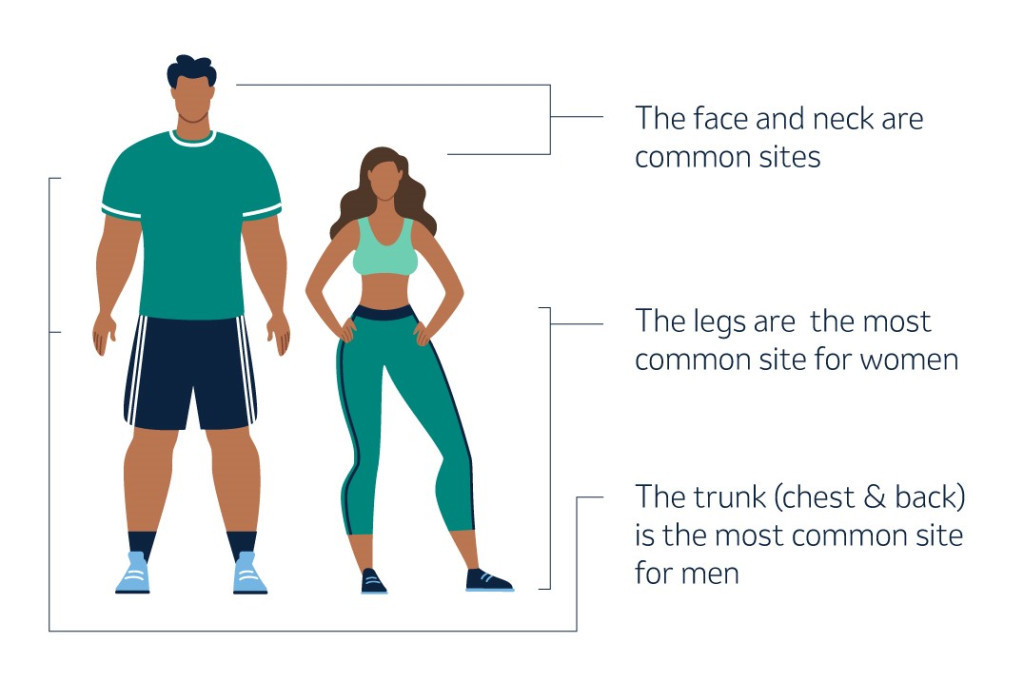

Melanoma can occur anywhere on the skin, including areas without sun exposure, but it’s more likely to start in certain locations, like the face and neck, legs (most common in women), and chest and back (most common in men).